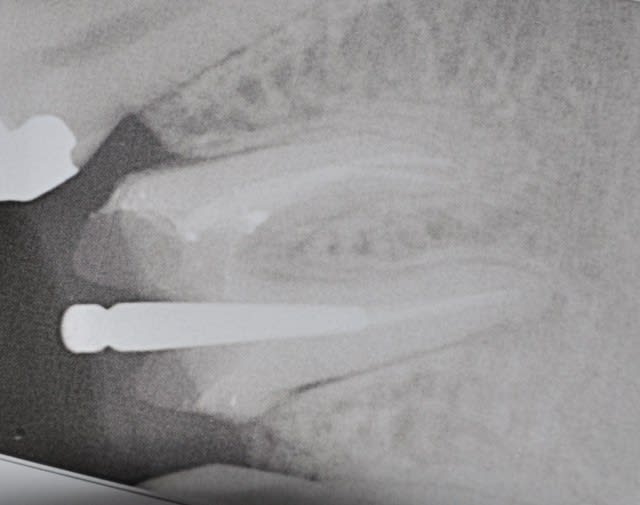

Blette

retour de dubai, fissure du plancher radiculaire et lime apicale....

Dsc 0224 wmdwee - Eugenol